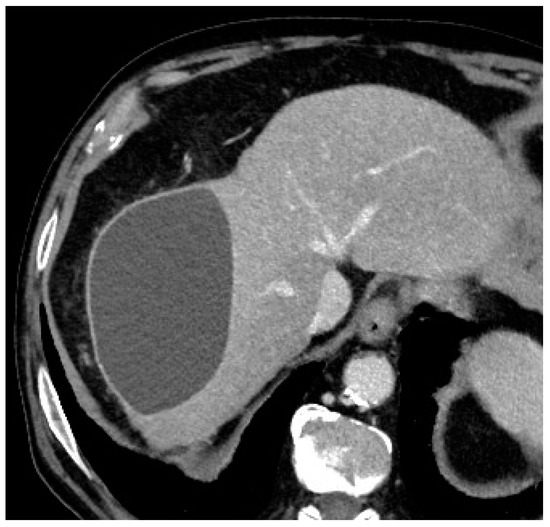

In terms of complications, graded according to the National Cancer Institute Common Terminology Criteria for Adverse Events (NCI-CTCAE) version 3.0, only one (7.7%) intra-procedural complication was registered, consisting of microcatheter blockage during microsphere injection, with no threat to the patient’s health (grade 0 according to NCI-CTCAE) [12]. This blockage was completely and promptly resolved by performing a careful and slow flushing of saline through the microcatheter until a correct flow was restored inside the microcatheter and inside the target vessel. At the 1-month follow-up imaging, two patients (15.4%) had a progressively increasing biloma (Figure 2), which required additional treatment (grade 3 according to NCI-CTCAE): in particular, one patient underwent percutaneous drainage by an interventional radiologist, while the other patient underwent surgical resection of the biloma.

Figure 2. Axial contrast-enhanced CT scan showing an 11 cm × 7 cm × 7 cm biloma in the VII hepatic segment at the 1-month post-procedural follow-up evaluation.